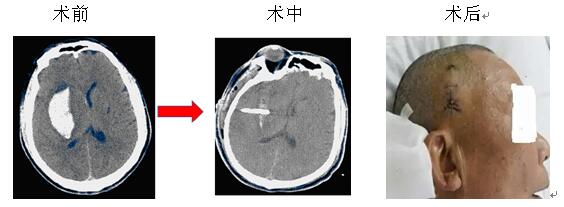

微創(chuàng)治療腦出血是指在CT或立體定向引導(dǎo)下,找到離血腫中心最近的位置,同時(shí)避開(kāi)重要的組織,用YL-I型針管一體裝置在電驅(qū)動(dòng)下安放引流管、抽吸血凝塊,減少血腫體積,達(dá)到清除血腫的目的。此方法創(chuàng)傷微小,操作快捷,費(fèi)用較低,在有CT的醫(yī)療器械情況下即可實(shí)施,故對(duì)廣大病患,特別是老年多病的腦出血患者而言是一種不二的選擇。

院神經(jīng)內(nèi)科率先在衡陽(yáng)地區(qū)實(shí)施微創(chuàng)治療腦出血,現(xiàn)經(jīng)救治的病患已達(dá)3000余人次,絕大部分患者得到好的結(jié)果,較少的死亡率,較輕的致殘率。本院將繼續(xù)提供較好的治療和服務(wù),來(lái)滿(mǎn)足病友的需求,也歡迎病友垂詢(xún)。